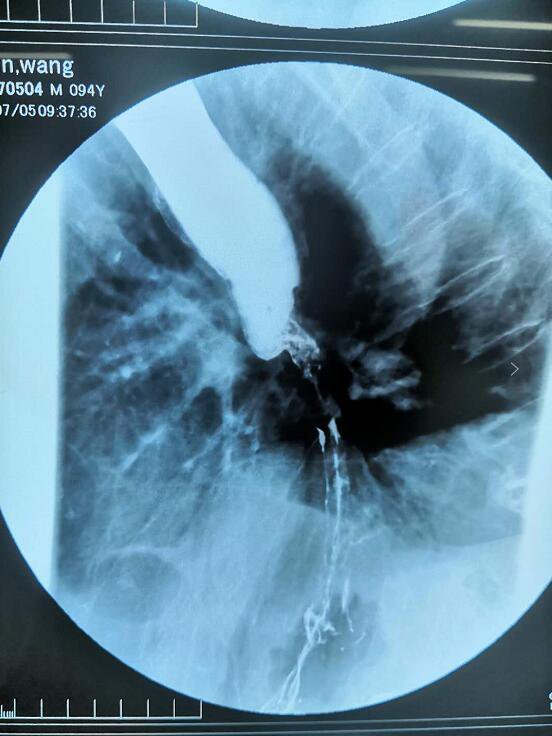

患者现进食流质饮食即有梗阻感,伴呕吐粘液样物质及反酸不适。根据目前情况考虑食管癌不全梗阻。反复与患者家属沟通治疗方案后,患者及家属接受食管支架植入治疗。术前完善行消化道钡餐显示:食管下段管腔局限性变窄,管壁僵硬,粘膜中断破坏,上段食管代偿性扩张。(见图1)